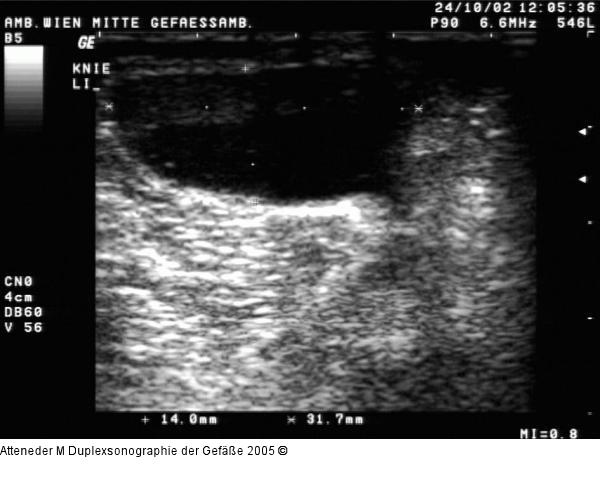

Abbildung 20: Duplexsonographie - Bakerzyste Bakerzyste im Querschnitt; echoarme Raumforderung in der Kniekehle |

Bakerzyste im Querschnitt; echoarme Raumforderung in der Kniekehle |